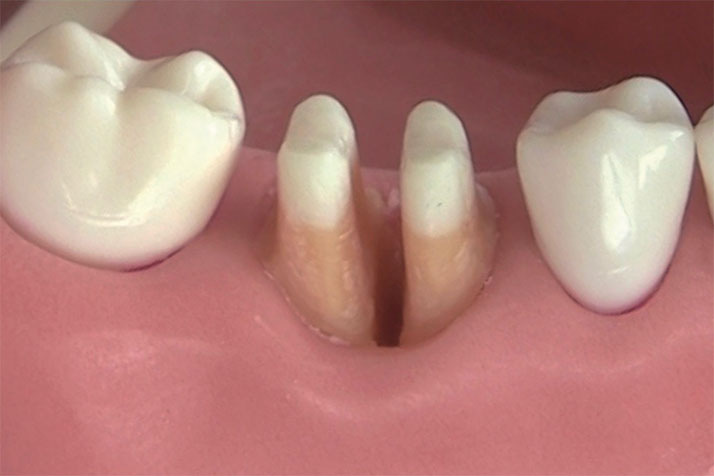

歯周病の原因

歯周病は、歯ぐきや歯を支える骨に炎症が起き、少しずつダメージが広がる病気です。原因の多くは、歯の表面に溜まった歯垢や歯石に潜む細菌です。これが歯ぐきに炎症を起こし、進行すると骨にまで影響します。

初期は痛みや自覚症状がほとんどないため、気づかないうちに進んでしまうこともあります。また、喫煙や糖尿病、ストレス、生活習慣の乱れも歯周病を悪化させる原因になります。こうしたリスクを放っておくと、最悪の場合、歯を失うことも。毎日の歯磨きと定期検診でお口の健康を守ることが大切です。